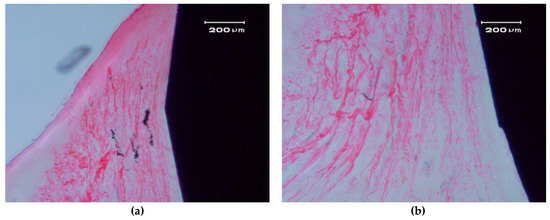

Figure 6.

Bone apposition on the surface of a ZCe-A implant after eight weeks of healing (longitudinal cross-section). The bone in contact with the implant shows a lamellar and Haversian structure. (a) left side and (b) right side of the implant

In the hard tissue area, a direct and close apposition of the bone matrix to the implant surface is observed, without the presence of a non-mineralized connective tissue interface.

The soft, gingival, peri-implant tissue is found to be in perfect contact with the implant. There is a close epithelial adhesion to the implant surface (Figure 7a) without lymphocytic infiltrate, disruption of the keratinized gingival structure, or alterations of the connective tissue attachment (Figure 7b). Secondary and tertiary osteons and vascular buds are seen nearby the implant’s surface (Figure 7a). Bone grows inside the thread’s valleys in intimate contact with the implant and very clear reversal lines can be observed delineating the different stages of bone remodeling (Figure 7b). There are no signs of inflammation or implant rejection by the bone, nor atypia or dysplasia.